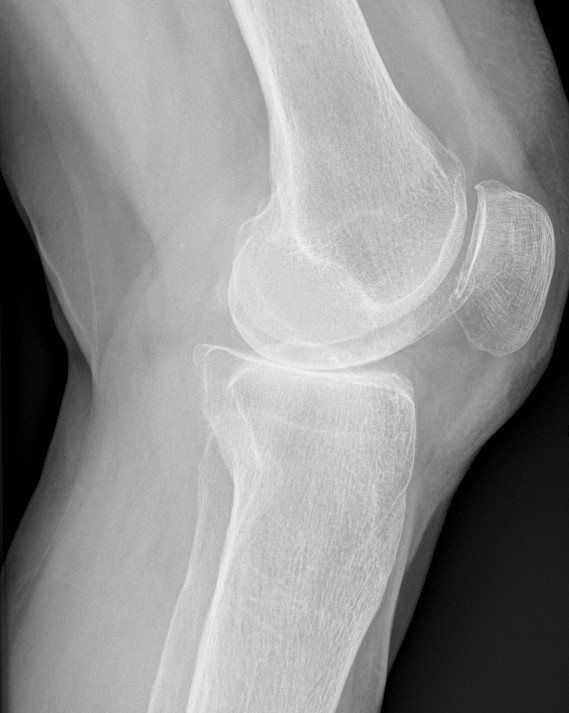

3. Patella Baja